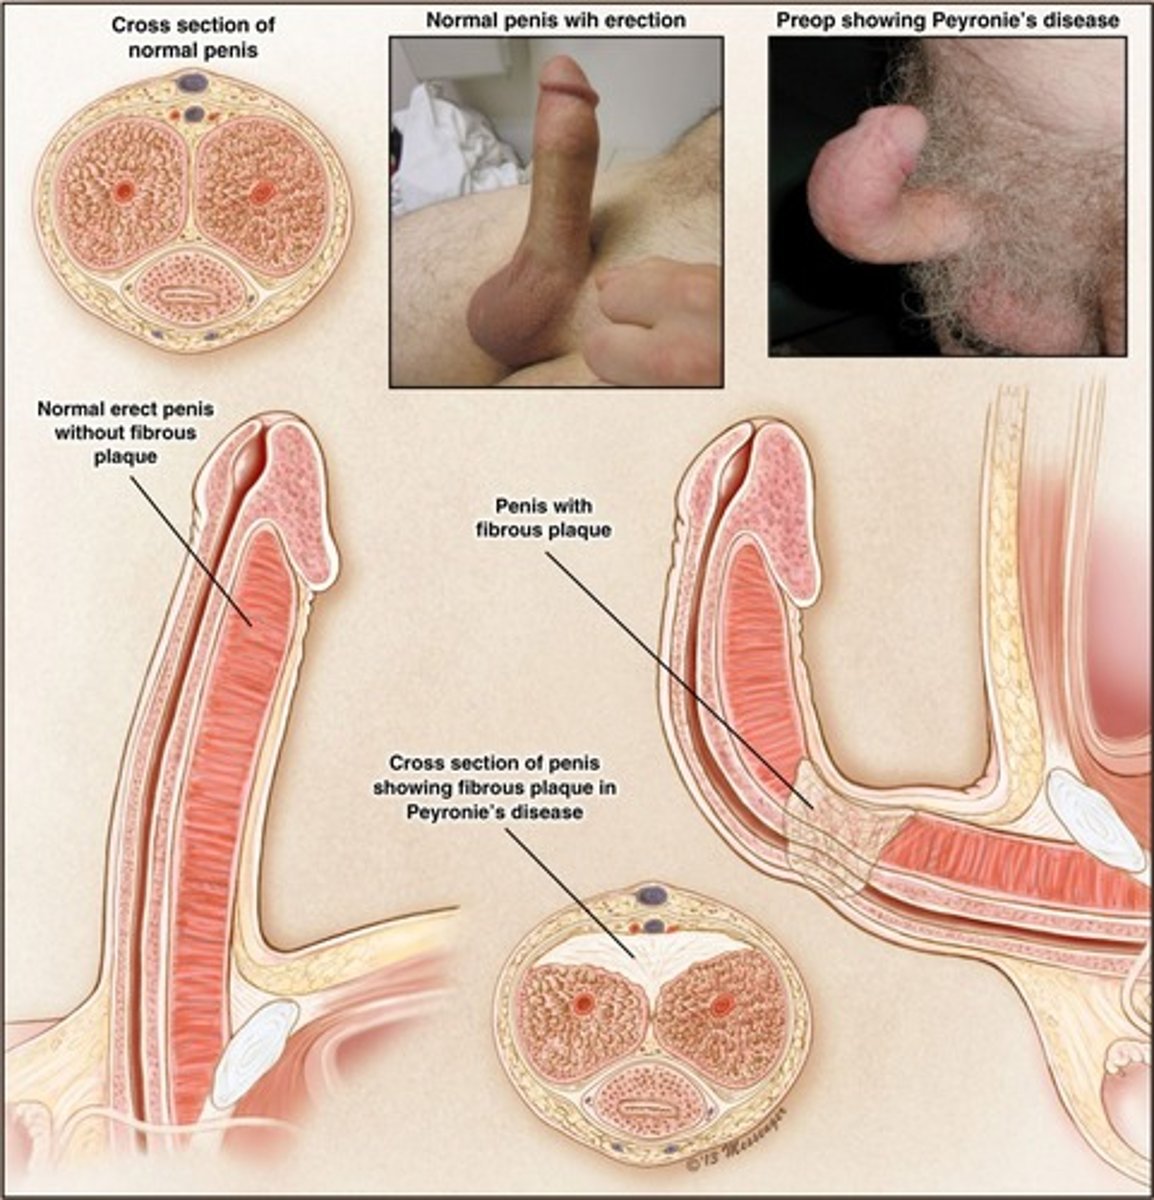

Fibrous plaques in soft tissue of penis with abnormal curvature

Peyronie disease (connective tissue disorder)